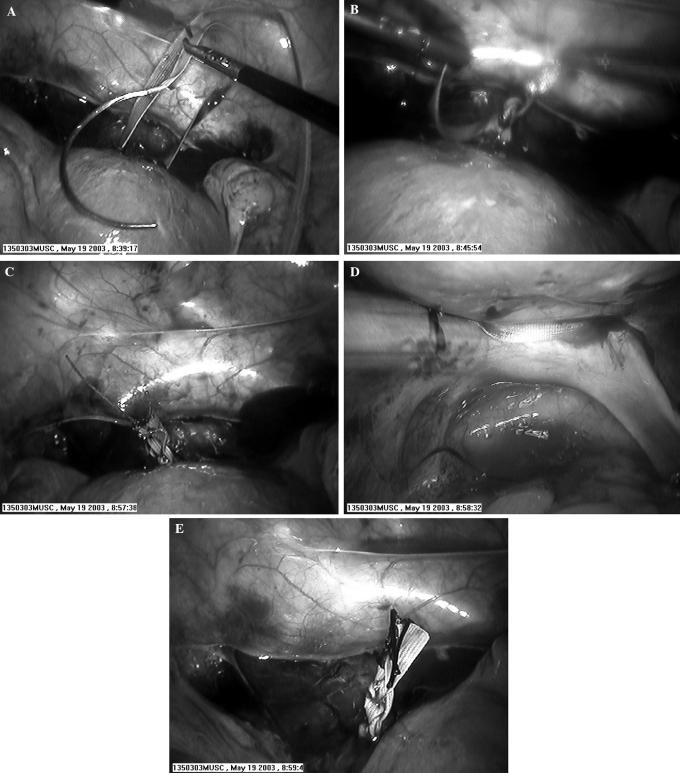

Laparoscopic abdominal cerclage.

Abdominal cerclages are necessary when the standard transvaginal cerclages fail or anatomical abnormalities preclude the vaginal placement. The disadvantage of the transabdominal approach is that it requires at least 2 laparotomies with significant morbidity and hospital stays. We discuss a case of abdominal cerclage performed laparoscopically. We feel it offers less morbidity and in the proper hands eliminates or significantly shortens hospital stays.